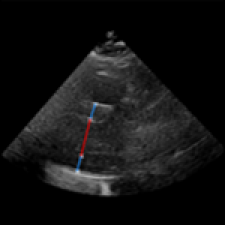

| (a) LV Measurements | (b) Label Smoothing |

Left Ventricular Hypertrophy (LVH), one of the leading predictors of adverse cardiovascular outcomes, is the condition where heart’s mass abnormally increases secondary to anatomical changes in the Left Ventricle (LV) [10]. These anatomical changes include an increase in the septal and LV wall thickness, and the enlargement of the LV chamber. More specifically, Inter-Ventricular Septal (IVS), LV Posterior Wall (LVPW) and LV Internal Diameter (LVID) are assessed to investigate LVH and the risk of heart failure [21]. As shown in Figure 1 (a), four landmarks on a parasternal long axis (PLAX) echo frame can characterize IVS, LVPW and LVID, and allow cardiac function assessment. To automate this, machine learning-based (ML) landmark detection methods have gained traction.